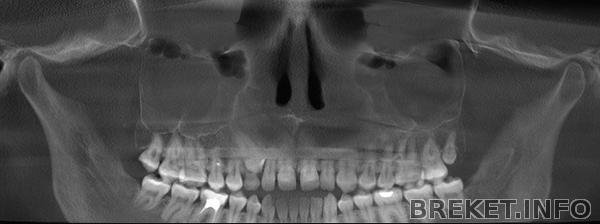

Решила тут сравнить КТ сразу после оп. по рассечению нёбного шва, сразу после расширения и после снятия аппарата.

тут уже есть небольшая диастема, которую раскручивают во время операции

тут расширение видно во всей красе